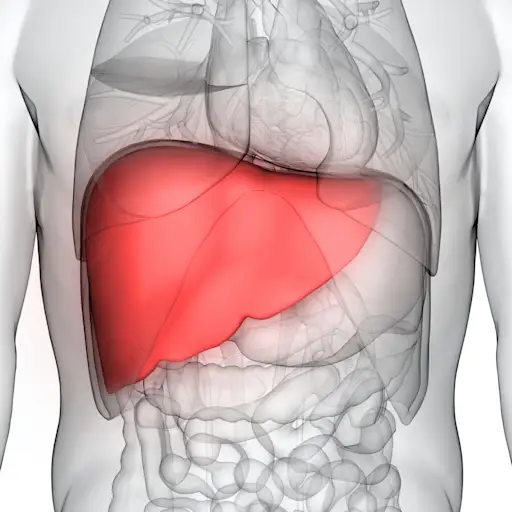

当你有attrc - cm时,一种由你的肝脏产生的蛋白质转体基因)分解,然后聚集在一起形成所谓的淀粉样纤维.问题是,你的身体无法摆脱这些结块。相反,它们在不同的器官中积累,造成严重破坏。“当这种情况发生在心脏时,心脏会变硬,”卡马尔博士解释说。随着时间的推移,这种硬化会导致心脏衰竭,心脏不能有效地泵血。有时,基因突变会导致在attro - cm中发现的蛋白质问题,但更常见的原因是未知的。这就是所谓的野生型ATTR-CM.